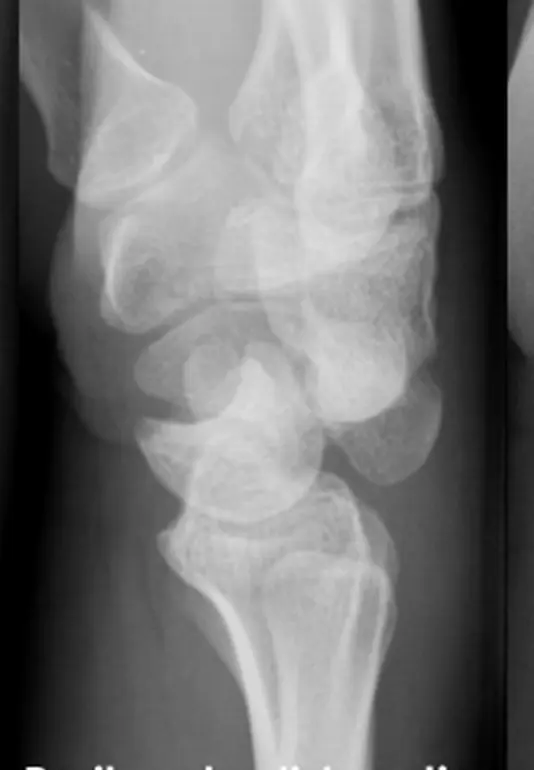

- الأشعة السينية (X-rays): هذه هي الخطوة الأولى والأكثر أهمية في تشخيص خلع الرسغ. سيتم أخذ عدة صور بالأشعة السينية من زوايا مختلفة (أمامية خلفية، جانبية، مائلة) للكشف عن أي انزياح في العظام الرسغية. في حالة خلع الرسغ المحيط بالعظم الهلالي، قد يلاحظ الأستاذ الدكتور محمد هطيف وفريقه علامات مميزة مثل "علامة الوعاء المقلوب" (Spilled Teacup Sign) في الأشعة السينية الجانبية، والتي تشير إلى انزلاق العظم الهلالي من مكانه الطبيعي، أو انزياح العظم الكبير خلف العظم الهلالي (كما هو الحال في هذه الإصابة المحددة).